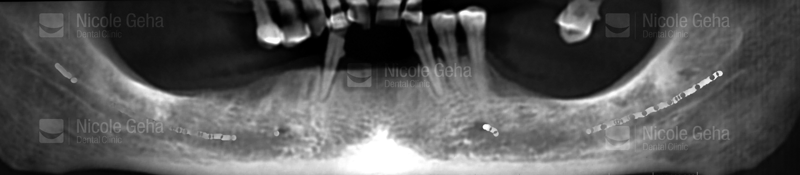

Before extraction and implants